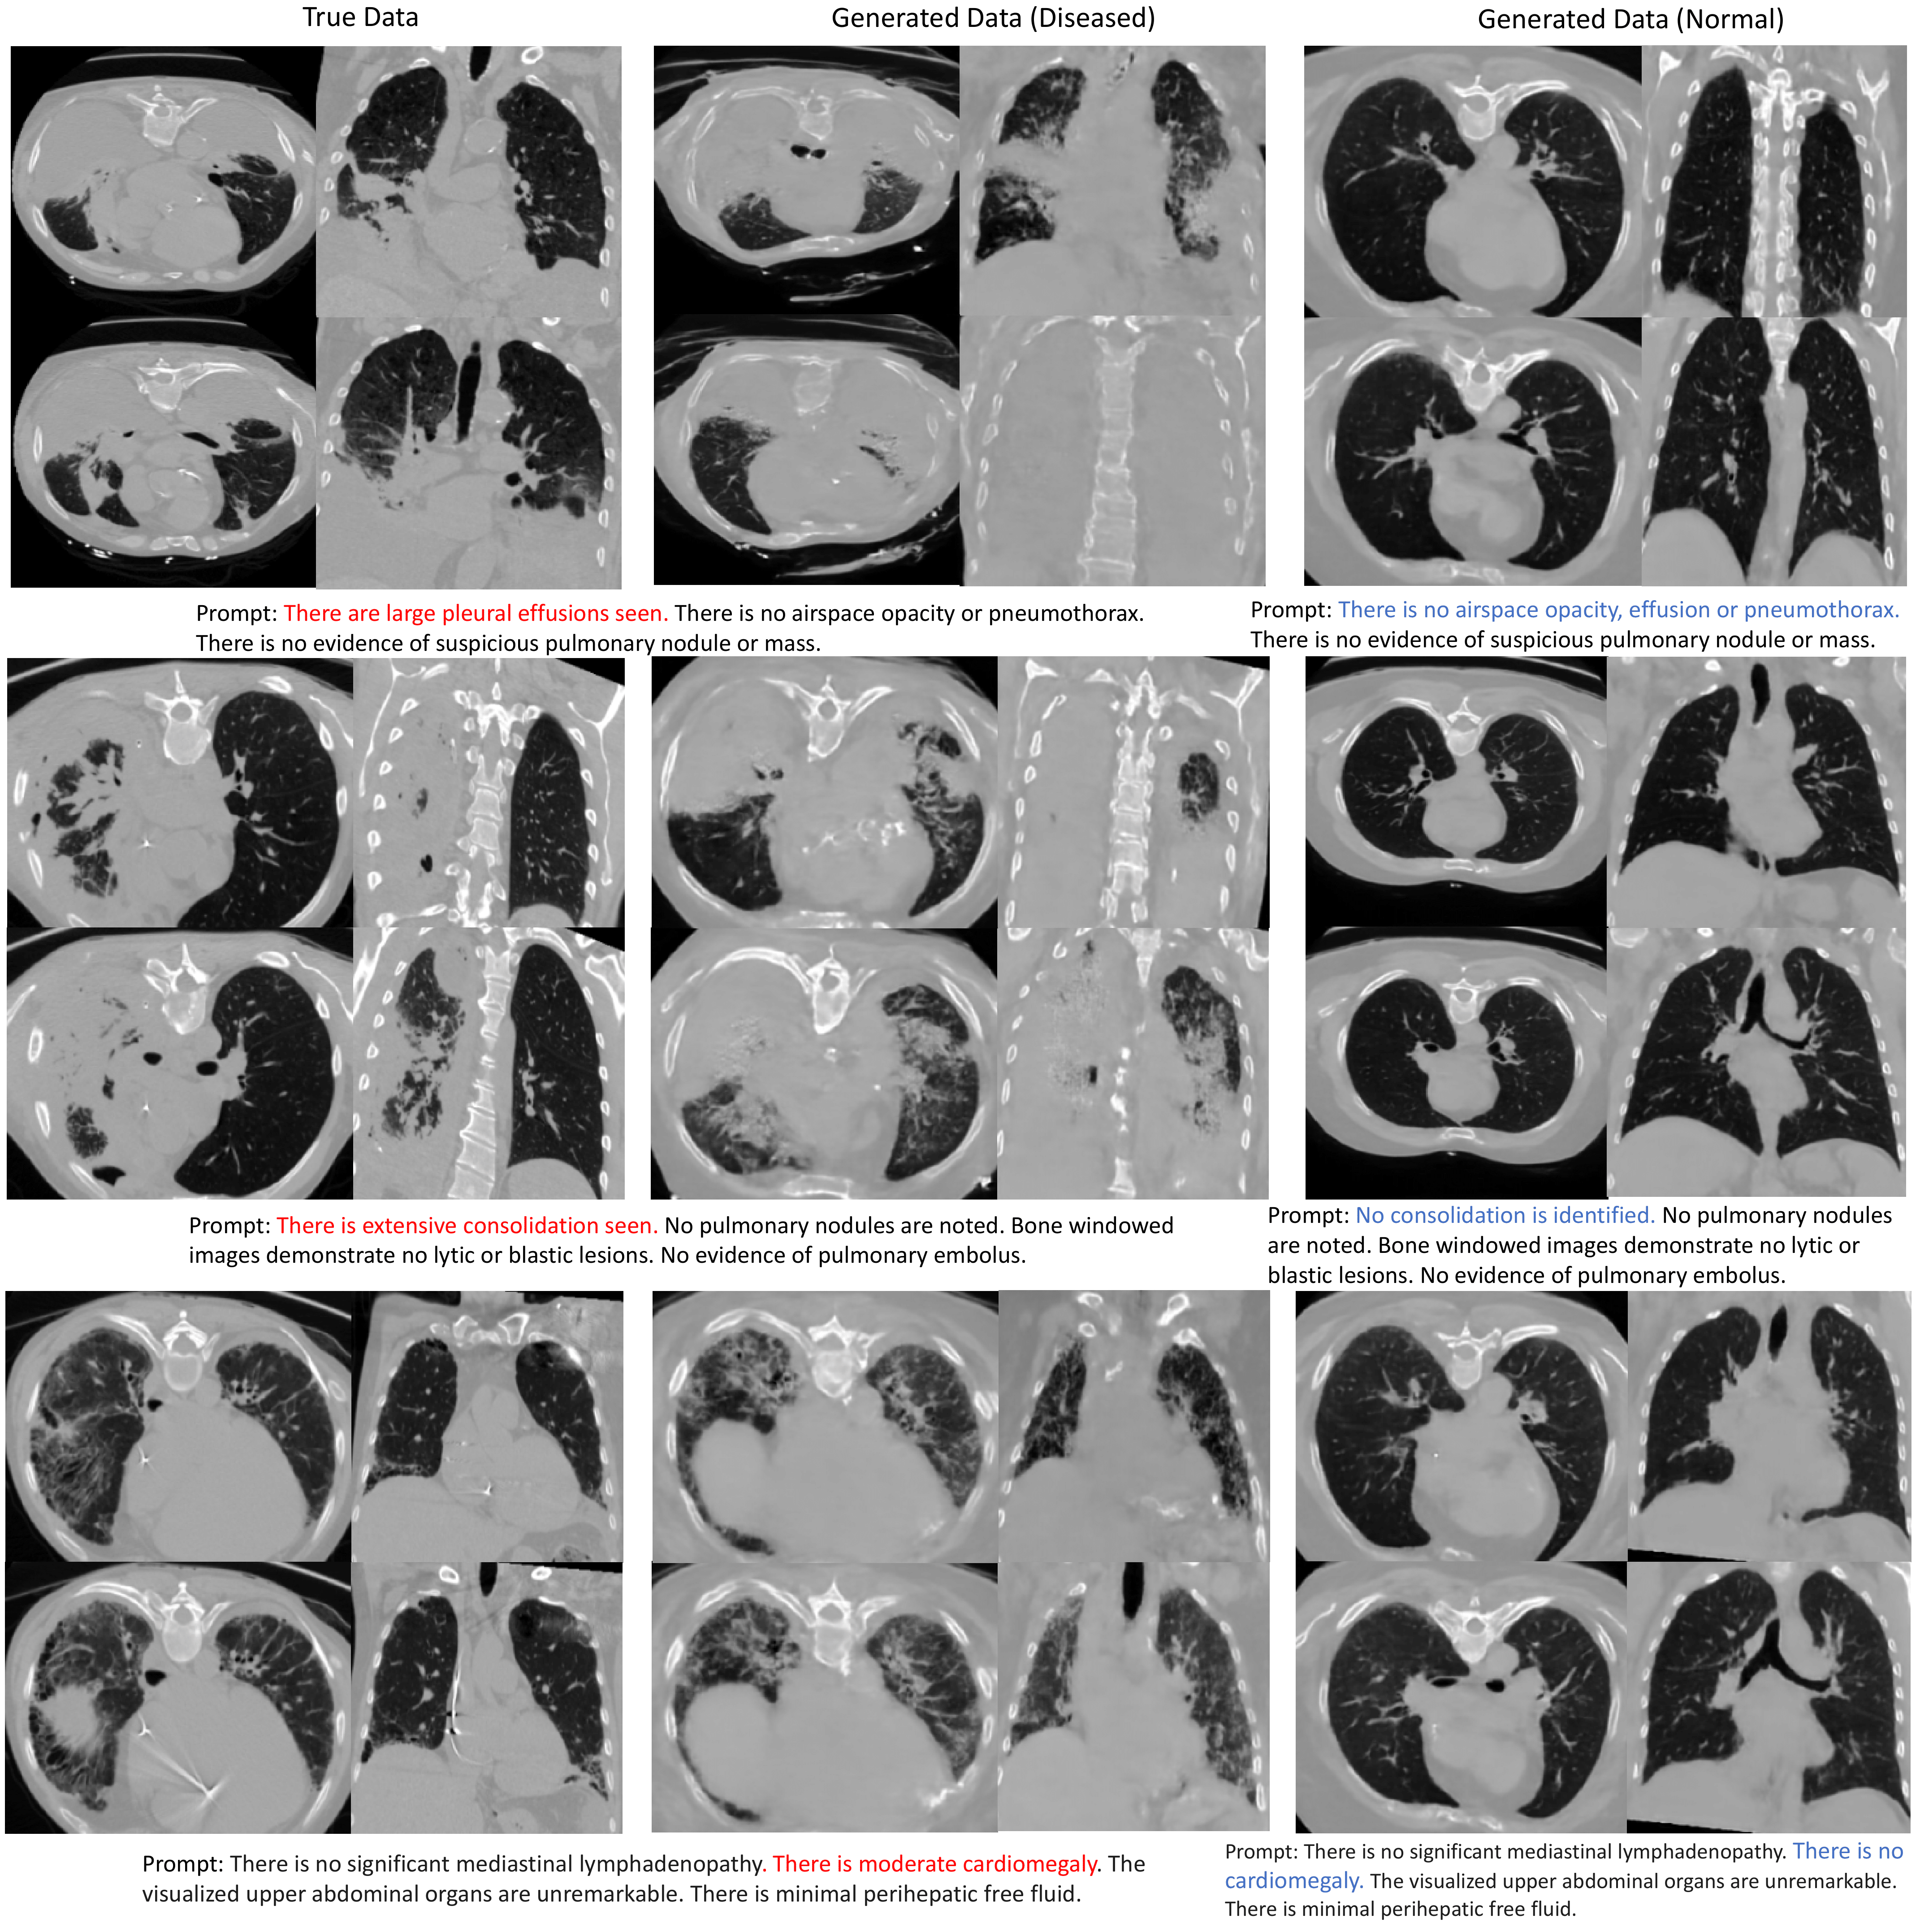

Refer to caption

Figure 4: Images conditionally generated with disease-related prompts. We show the real images in the first two columns. Then we extract disease-related mentions from their associated reports as conditions to generate images, which are shown in the third and fourth columns. We also show the synthesized samples by conditioning on prompts reversed of the disease in the last two columns. Four slices are shown for each subject.

In this section, we perform experiments to study the relevance of generated images in response to specific input prompts, specifically on pleural effusion, bullous emphysema, and cardiomegaly. First, we build prompt pairs by selecting prompts from real reports that contain descriptions about certain pathology (e.g. There are large pleural effusions seen), and reversing its description (e.g. There is no pleural effusion) to build its prompt pair. The prompts used here can be found in Fig. 4. Then, we use our model to generate images conditioning on the original prompts and the modified prompts, respectively. Conditioned on each prompt, we generate 32 CT volumes and perform quantitative analysis to measure the alignment between the synthetic images and the abnormality condition specified in the prompt. For pleural effusion, we use Total Segmentor [34] to segment the effusion from generated images and measure the volume. For bullous emphysema, we measure the %LAA-950 (percentage of low attenuation areas less than a threshold of -950 Hounsfield units) for generated images. For cardiomegaly, we use Total Segmentor [34] to segment the heart and lung region from CT volume, and then we compute the cardiothoracic ratio (CTR) by measurement of the maximal cardiac width divided by the maximal thoracic width at the same axial scan level. The evaluation results for pleural effusion, bullous emphysema and cardiomegaly are shown in Table. 2,  4 and  4 respectively. For pleural effusion, we found that when conditioning on the prompt with “large effusion,” the generated images show a greater volume of pleural effusion compared to images synthesized with a prompt containing “no effusion.” For bullous emphysema, we found that the generated images conditioning on prompt containing “no bullae” have higher %LAA-950 values, which suggests more severe emphysema. For cardiomegaly, we found that when conditioning on the prompt with “There is cardiomegaly,” the generated images have higher CTR, which suggests a greater degree of cardiomegaly. We also provide the distribution of CTR in Fig. 5.

For the qualitative examples generated from our model, we chose those three distinct prompts paired with negative prompts to show the prompting effect on synthetic images. In Fig. 4, we show the volumes from the real and synthetic data with the text description and the negative prompting synthetic data. Our model shows the ability to generate unseen data and control the generative process through prompting.